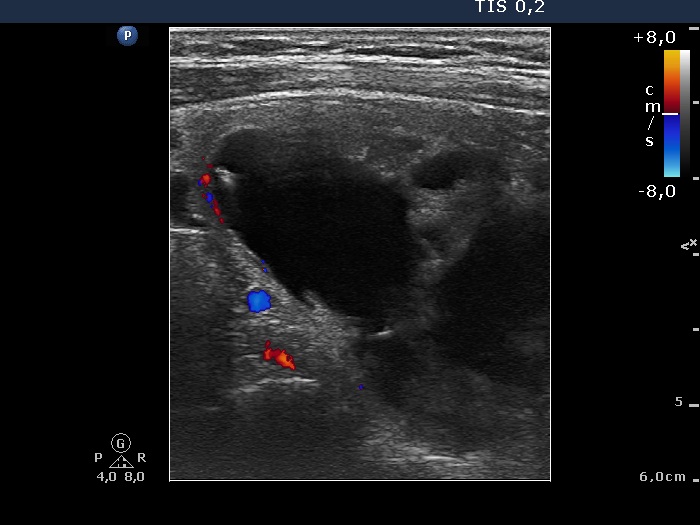

First investigation (first row of images)

Clinical data: a 64-year-old woman was referred for ethanol sclerotherapy. The patient was aware of a slowly growing nodule over more than 20 years. The patient suffered form cough and difficulties in swallowing for several months. These complaints were resolved for two days after aspiration of 30 mL cystic fluid for 3 weeks. However, the cyst has refilled within 2 days and her complaints have recurred. She had various diseases including ischemic heart disease, recurrent thrombotic events, therefore general anaesthesia would share a significant risk.

Palpation: a large hard nodule occupied the right lobe and the isthmus.

Functional state: euthyroidism (TSH 1.05 mIU/L).

Ultrasonography. The thyroid was echonormal. A large mixed nodule was found in the right lobe. The solid part of the lesion was echonormal, and the nodule presented signs of a type 2 vascular pattern.

27 mL cystic fluid was aspirated thereafter 7.2 mL absolute alcohol was administered. The patient had no significant complaints.